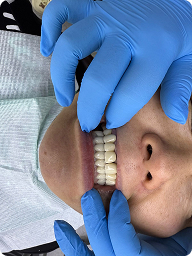

Вторичная имплантация: даём второй шанс

Не каждая клиника готова качественно справиться с полной реконструкцией зубного ряда. Это сложная операция, требующая системного подхода.

В нашей клинике используется цифровая система планирования, что позволяет точно спланировать место установки каждого импланта, минимизировать хирургическое вмешательство и сразу же установить индивидуальные протезы.